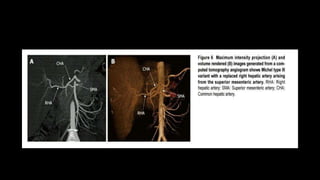

LIVER VASCULAR SYSTEM •Around 25% of hepatic blood inflow is arterial and is supplied by the common hepatic artery (CHA). • Portal vein supplies ~75% of the liver's blood supply by volume. • Most of the venous drainage from the liver passes into the three hepatic veins which drain into the inferior vena cava.

• 39.

HEPATIC ARTERY • Atthe liver hilum, before entering the parenchyma, the hepatic artery bifurcates into the right and left hepatic branches. • The right hepatic artery (RHA) is larger, gives off a cystic branch for the gallbladder and bifurcates into anterior and posterior branches just before entering the parenchyma. • The left branch divides into three vessels for the anterior, posterior and caudate parts of the left lobe. • Hepatic arteries then give off segmental and subsegmental arteries that run and branch in the portal spaces.